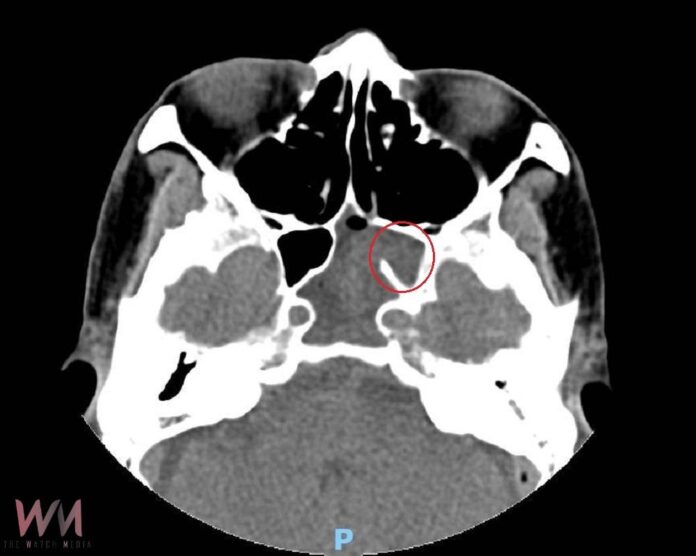

加護病房主任林文培指出,起初懷疑是腦膜炎,但經腦部影像檢查後排除,進一步透過電腦斷層與核磁共振檢查,發現李先生鼻腔最深處的左側蝶竇出現異常影像,研判為膿瘍形成,壓迫第3至第6對腦神經,導致頭痛、複視與神經相關症狀,隨即轉介神經內科及耳鼻喉科進行會診。

耳鼻喉科主任許嘉方說明,蝶竇位於鼻腔最深處,鄰近腦部重要神經,一般鼻竇炎多見於與過敏或感冒相關,極少見單一蝶竇發炎。李先生的情況屬臨床罕見案例,且病況惡化迅速,抗生素已無效,經緊急安排內視鏡手術清除膿瘍。